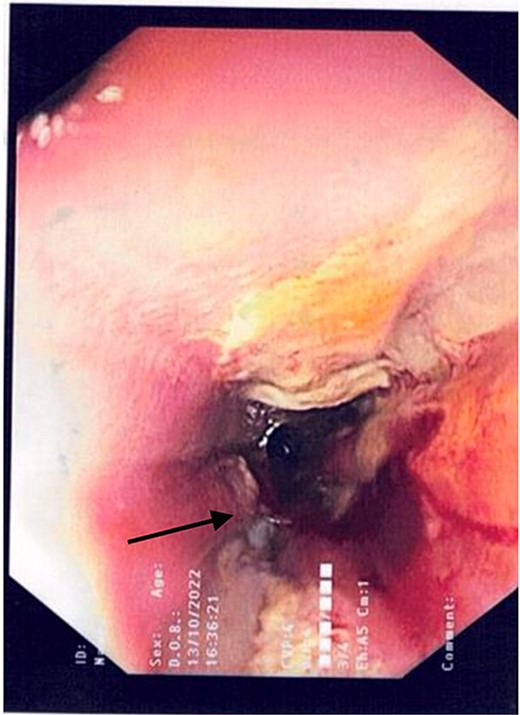

2L of pus was evacuated during laparoscopy, and it was converted to open due to limited views. At this stage, there was no obvious perforation. The entire colon was inspected, following splenic flexure and caecal mobilization. On inspection of the stomach, the wrap was intact with an unremarkable leak test. The decision was made to proceed with gastroscopy, whereby a 3 mm pinhole defect was seen at the GOJ at the 9 o’clock position, as shown in Fig. 2. Three haemostatic Cook Medical Instinct clips were placed, from distal to proximal, ensuring there was stable apposition of the perforated mucosa prior to deploying, as demonstrated in Fig. 3. Following this, the NGT was re-inserted under vision. The midline laparotomy was partially closed and Abthera dressing placed. The patient was taken to ICU intubated, with definitive closure performed 48 h later.

Gastroscopic image demonstrating the successful application of haemostatic clips at the site of perforation (arrow).

Total Parenteral Nutrition (TPN) was commenced immediately post-operatively. His post-operative course was complicated with fevers, necessitating a CT abdomen pelvis on Day 5, which demonstrated ileus with no other complications, such as ongoing leak. The endoscopic clips are noted on this CT in Fig. 4. Indeed, NG feeds were commenced on post-operative Day 7, following ongoing high NG outputs necessitating 2-hourly aspirates. TPN was ceased on Day 13, and he was discharged on Day 14 with oral antibiotics, a thickened fluid diet, and an NGT. On follow up, his NGT was removed, and he was upgraded to a full diet.

Intravenous and oral contrast enhanced CT abdomen/pelvis on post-operative Day 5, in axial view, demonstrating the placement of haemostatic clips at the previous site of perforation (arrow), with no evidence of ongoing leak.